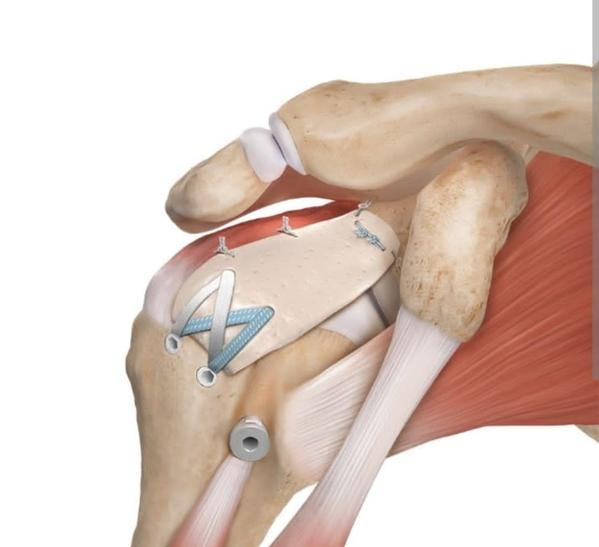

frozen shoulder treatment near me